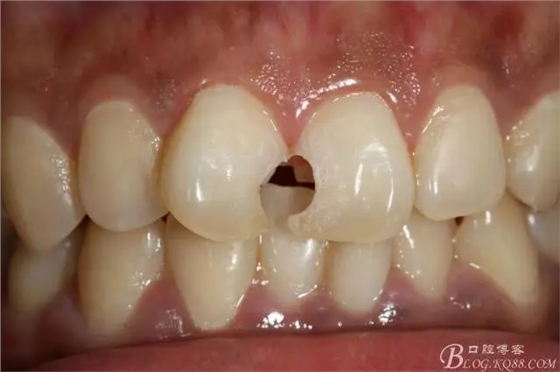

3mz250充填完成即刻照

2016.1復(fù)查情況很不好,再次建議做瓷貼面并告知各自優(yōu)缺點(diǎn)。這回患者同意并選擇鑄瓷貼面。